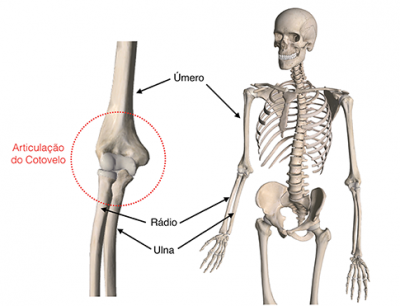

Início / Anatomia do Cotovelo / FIGURA-1

- Anatomia do Cotovelo

- Fraturas no Cotovelo (úmero, ulna e rádio)

FIGURA-1